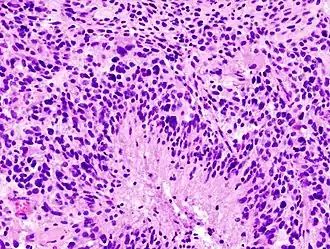

.jpg)